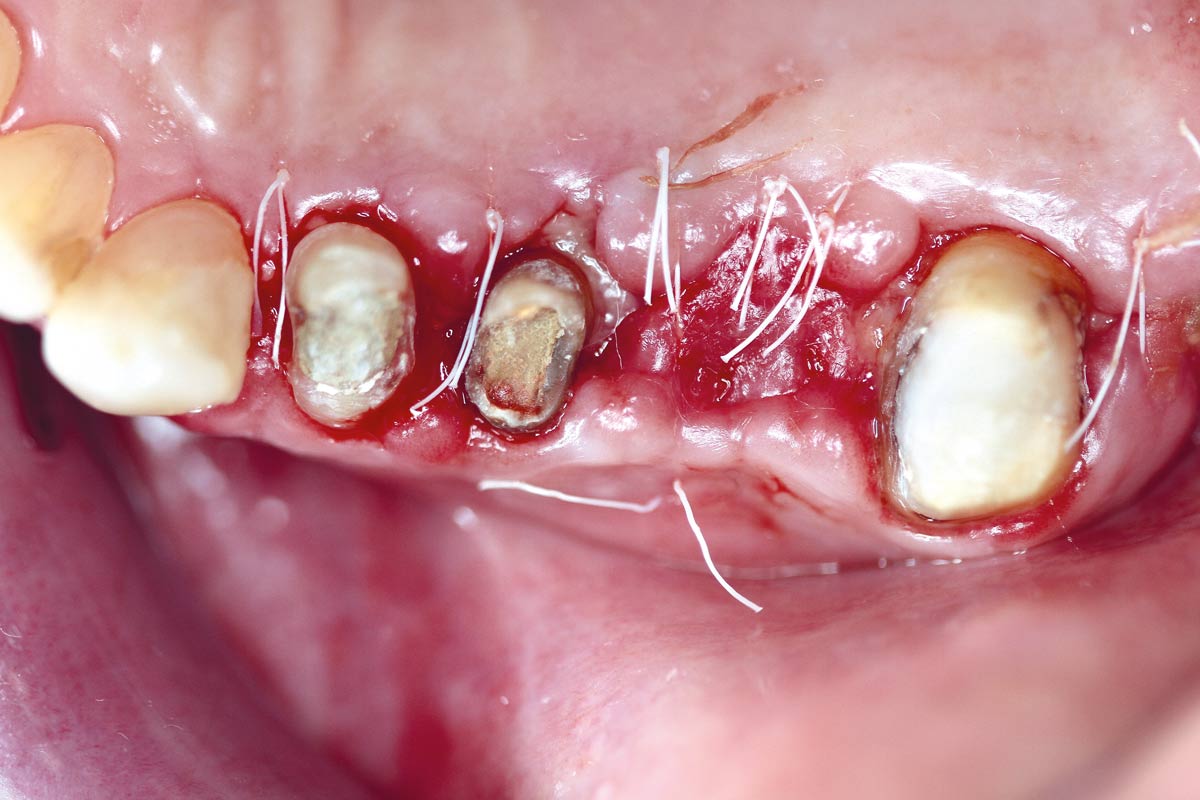

botiss-cerabone-permamem-maxgraft-mucoderm-horizontal-gbr-maghaireh

Initial situation - A young female 34 years old lost her front teeth in an surfing accident and she had a 5 unit bridge supported by her upper left lateral and right canine. The restoration failed and both supporting crowns have exposed and leaking margins.